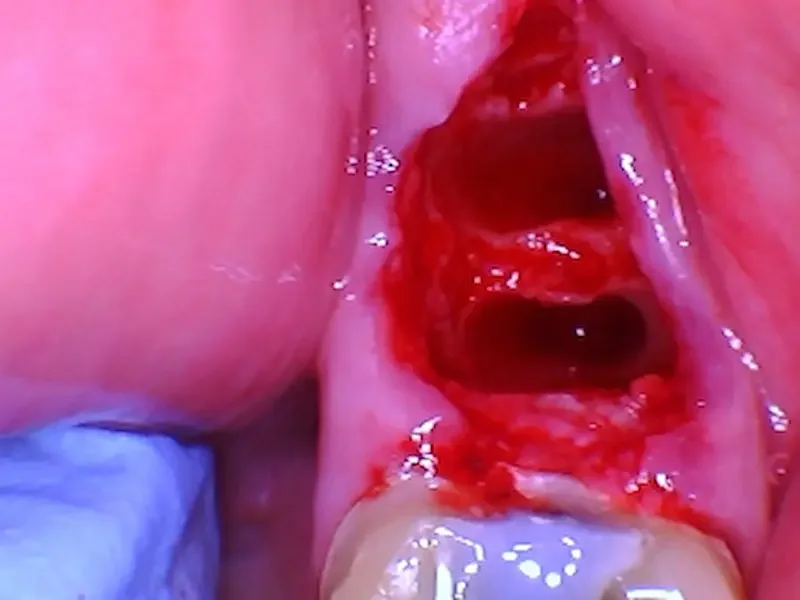

After gentle removal, the socket (the bony hole where the roots sat) is clearly visible.

The socket after gentle extraction.

*note for the adjacent tooth - we also did crown #19 that day, and this was before we cemented the temporary crown.

✅ Goal: Gentle extraction maintains socket integrity, keeping bone walls present, and prevents early bone collapse.